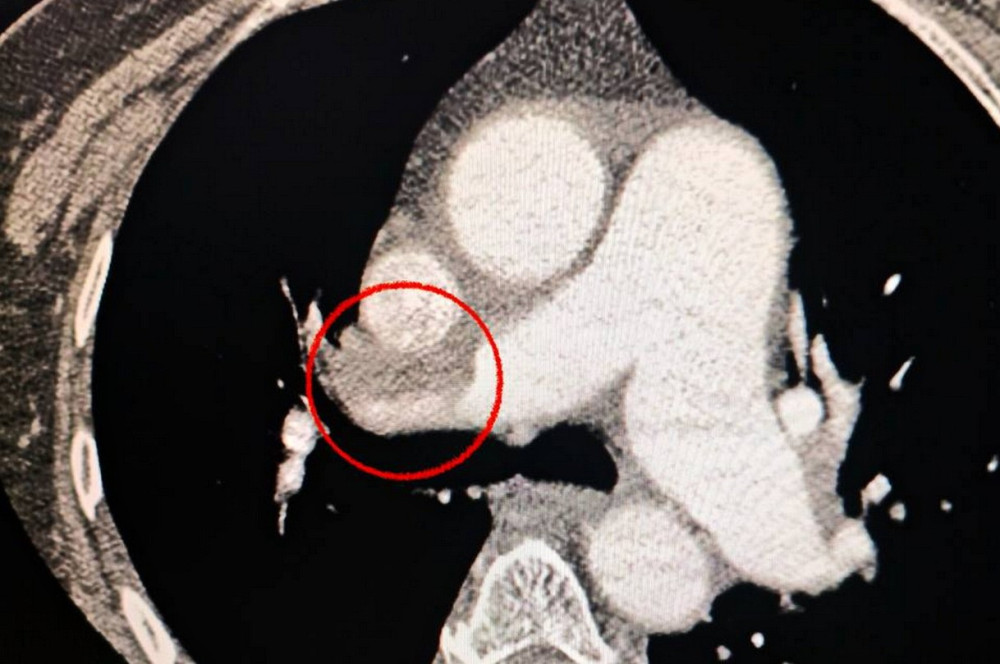

Уникальная хирургическая операция в Одессе

В Одесской больнице успешно проведена уникальная операция по лечению инсульта и тромбоэмболии.

Новые подходы к лечению инсульта: опыт одесских врачей